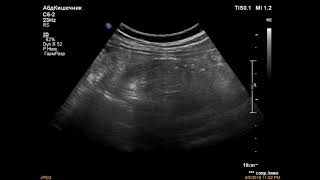

Низкий вес плода и УЗИ